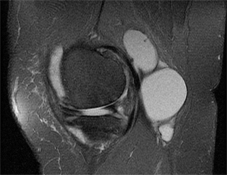

Septated Baker's Cyst